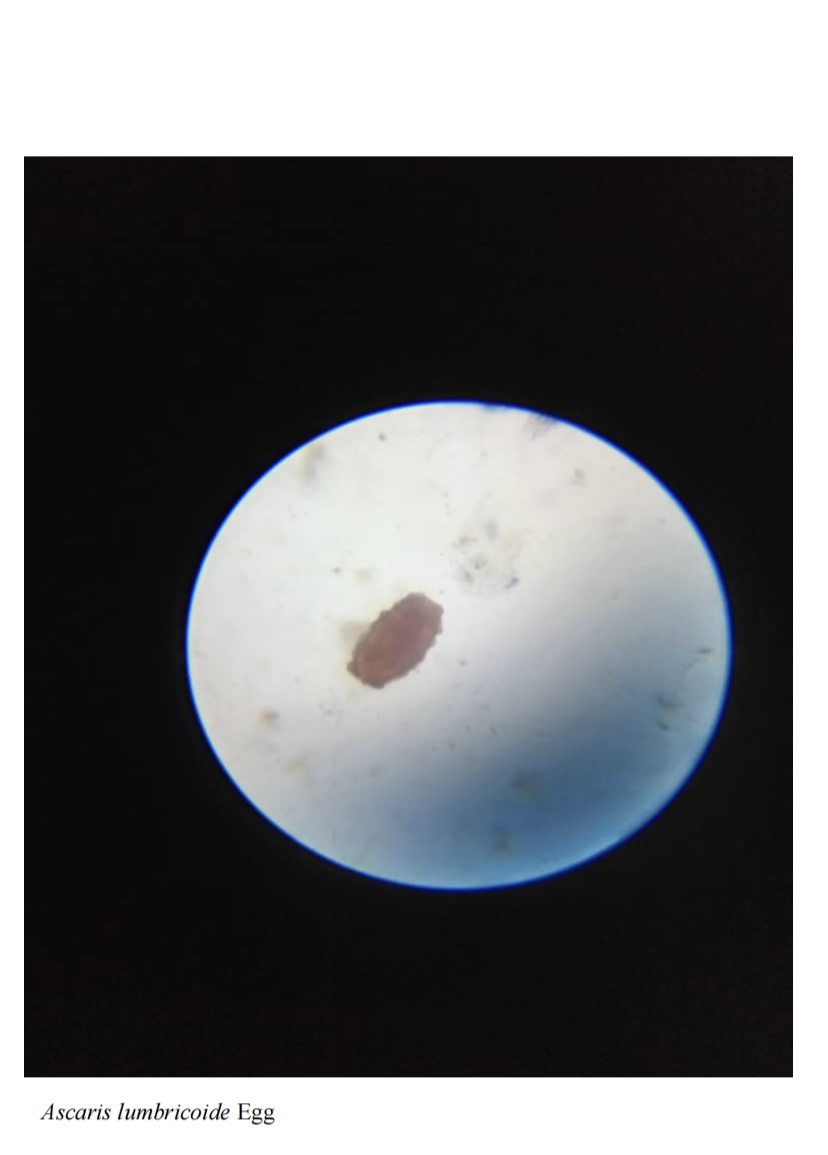

Prevalence of Gastrointestinal Parasites Among Children in Remand Orphanage Home

Student: Chidimma Chinwendu Ani (Project, 2025)

Supervisor: Dr Imalele Edema

Co-supervisor: Dr Imalele Edema

HOD: Dr Raymond Ajang

Department of Zoology and Environmental Biology

University of Calabar, Calabar, Cross River State

View Submission